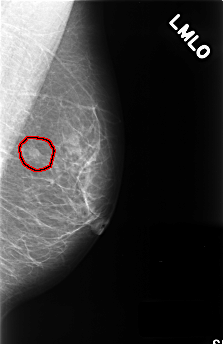

C_0388_1.LEFT_MLO

LEFT_MLO LINES 4472 PIXELS_PER_LINE 2896 BITS_PER_PIXEL 12 RESOLUTION 50 OVERLAY

FILE: C_0388_1.LEFT_MLO.OVERLAY

TOTAL_ABNORMALITIES 1

ABNORMALITY 1

LESION_TYPE MASS SHAPE LOBULATED MARGINS CIRCUMSCRIBED

ASSESSMENT 3

SUBTLETY 5

PATHOLOGY BENIGN

TOTAL_OUTLINES 1

BOUNDARY